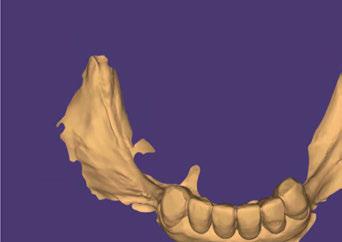

Figuras 9 y 10. El primer paso para iniciar la rehabilitación se realiza mediante un escaneado intraoral para poder generar unos modelos tridimensionales exactos de la paciente elaborados mediante flujo digital y sobre ellos crear un encerado que nos dé la oclusión buscada y la posición ideal de los dientes a reponer.

Figuras 11 y 12. Modelos realizados por CAD/CAM con los encerados de los dientes a reponer en los sectores posteriores mandibulares, montados en el articulador para generar una oclusión óptima.